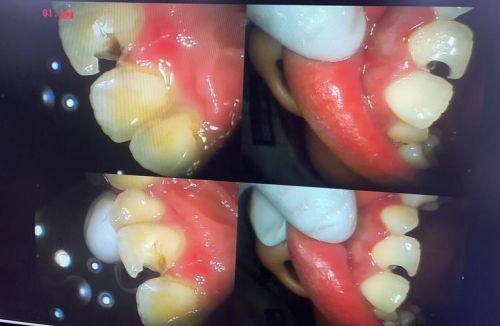

补牙会不会越补越烂,这得从补牙的原理说起。其实,补牙是治疗龋齿非常有效的一种方法。当我们的牙齿出现龋坏,也就是大家常说的“虫牙”,牙齿表面会发黑,这是细菌侵蚀牙齿导致的。医生在补牙时,会把牙齿上发黑的龋坏部分完全清理干净。就好比我们打扫房间,要把里面的垃圾都清除出去。清理完龋坏部分后,医生会使用专门的填充材料把牙齿坏的地方填补起来。在这个过程中,医生只会处理龋坏的部分,对于牙齿没有受损的部分是不会造成破坏的。所以,从补牙的原理来看,补牙本身是不会越补越烂的。它是在拯救我们的牙齿,让牙齿修复正常的功能和形态。